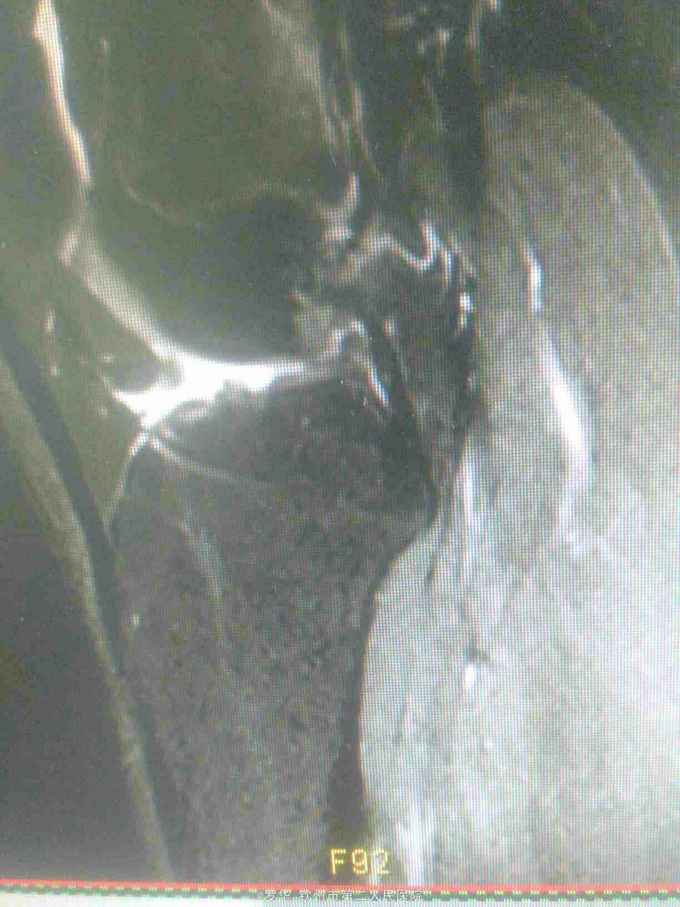

主诉:扭伤致左膝关节活动受限3月余。病史:患者男性,31岁,于入院3月余前扭伤左膝关节,致左膝关节肿痛、活动受限,尚可站立行走,但不能剧烈运动及重体力劳动,曾行磁共振检查提示左膝前交叉韧带损伤,半月板损伤,现为进上一步治疗入院。

查体:左膝关节无明显压痛,前抽屉试验阳性,侧方应力试验、麦氏征、研磨试验均阴性,膝关节屈伸活动可,余查体未见特殊。 辅查:膝关节磁共振提示左前交叉韧带损伤,左膝关节半月板损伤。

诊断:左膝关节前交叉韧带断裂,左膝关节半月板损伤。 治疗:予硬外麻下行左膝关节前交叉韧带重建术。

随访:术后三个月随访患者左膝关节屈伸活动可,无疼痛,上下楼梯,快速步行无疼痛感。 讨论:患者术后翻修率及对患肢运动限制。